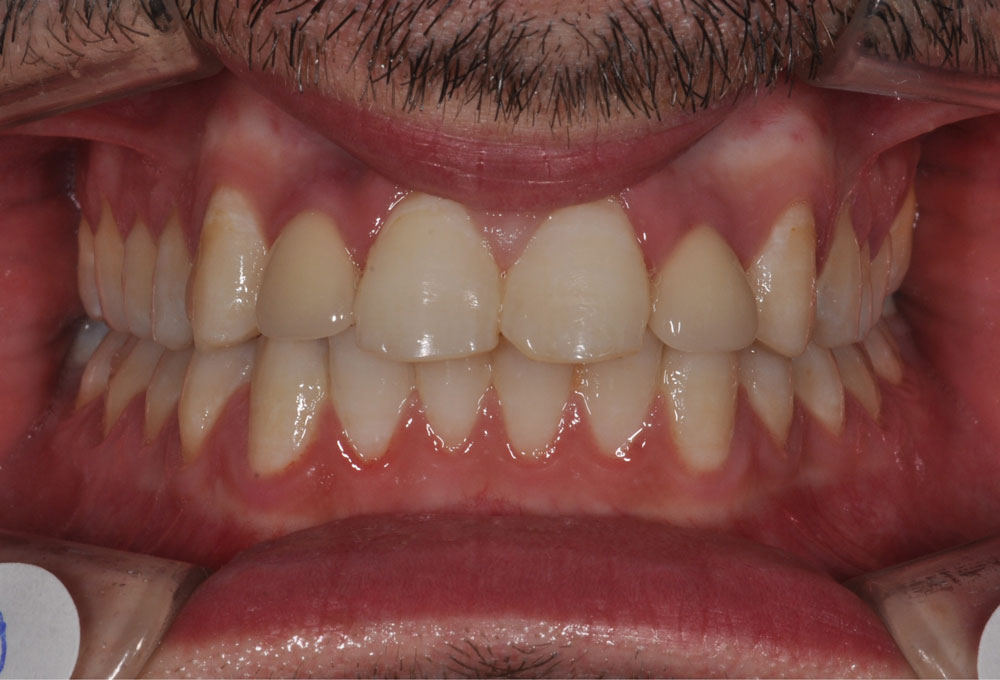

In questa terapia ortodontica si procede con il recupero dello spazio che sarebbe stato a disposizione dell’elemento del dente agenesico, al fine di una successiva sostituzione protesica dei denti mancanti.

Genericamente si ricorre a questa opzione nei casi in cui l’ingranaggio occlusale, la funzione masticatoria e l’estetica del sorriso siano già buoni.

La riapertura degli spazi viene eseguita per perfezionare le posizioni dentali e favorire la successiva riabilitazione protesica.

In questo caso, l’Ortodontista richiede la preventiva valutazione riabilitativa protesica al collega dentista, che fornirà le informazioni necessarie in merito alle future esigenze di spazio e posizione dentale per una miglior esecuzione del lavoro protesico previsto.